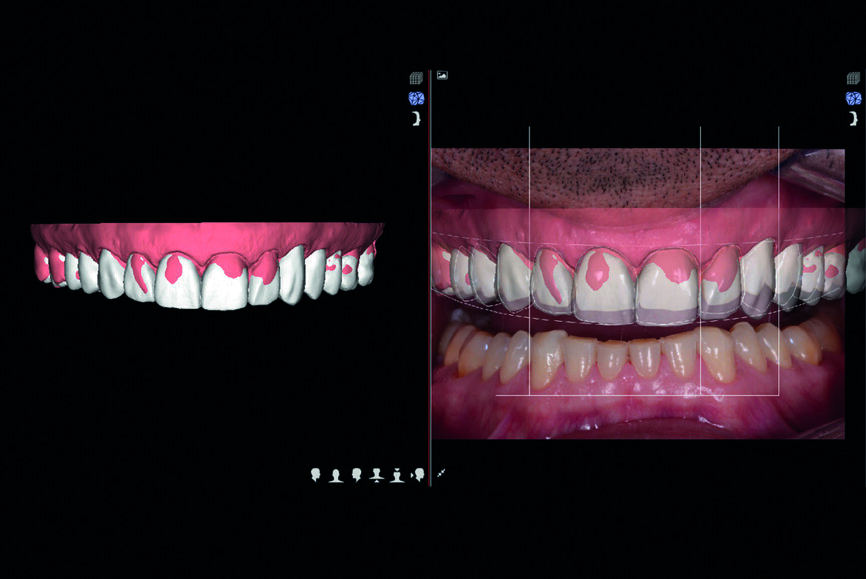

Fig. 9 : Planification DSD.

Quatre vidéos supplémentaires sont enregistrées aux fins de l’analyse fonctionnelle, structurale et faciale : consultation portant sur les attentes du patient, vidéo à 180° pour la composante phonétique, vidéo pour la composante fonctionnelle intraorale et vidéo pour la composante structurale intraorale avec écarteur labial et jugal (Fig. 5). Les données sont alors communiquées au laboratoire DSD. L’objectif principal du protocole DSD est de recréer les proportions correctes du sourire par une analyse des vidéos qui combine les images prises sous les trois angles (occlusal, de face et 12 heures) avec une échelle graduée numérique (cadre du sourire).

Le cadre du sourire est ensuite créé en plusieurs étapes tout en tenant compte de la symétrie faciale : arc facial numérique, morphologie et position de la ligne du sourire, largeur des dents déterminée au moyen de l’algorithme de la proportion dentaire esthétique récurrente (proportion RED - recurring esthetic dental proportion), profil du feston gingival, limite du vermillon et courbe de la mâchoire. Le logiciel CAD convertit les proportions 2D du sourire en un modèle numérique de simulation 3D. Le fichier 3D qui en résulte est transmis en format STL à une imprimante et celle-ci fabrique le modèle selon la nouvelle conception. Il est alors utilisé pour produire une matrice en résine bisacrylique (Structur 3, VOCO) qui servira de mock-up de confirmation (Fig. 6).

Les anciennes préparations des dents du second sextant ne sont pas modifiées. Aucune préparation n’est effectuée sur les dents postérieures supérieures (#14–17 et 24–27) et les dents postérieures inférieures (#34–37 et 44–47), les dents antérieures inférieures ne font l’objet que d’une préparation minimale. Une nouvelle empreinte numérique intraorale est prise. Les données sont communiquées au laboratoire DSD (Fig. 9) qui génère un fichier au format STL avec les modèles virtuels produits (Anatomic Lab). Ces modèles 3D (V-Print model, VOCO) sont élaborés dans une imprimante 3D (SolFlex 650, VOCO).